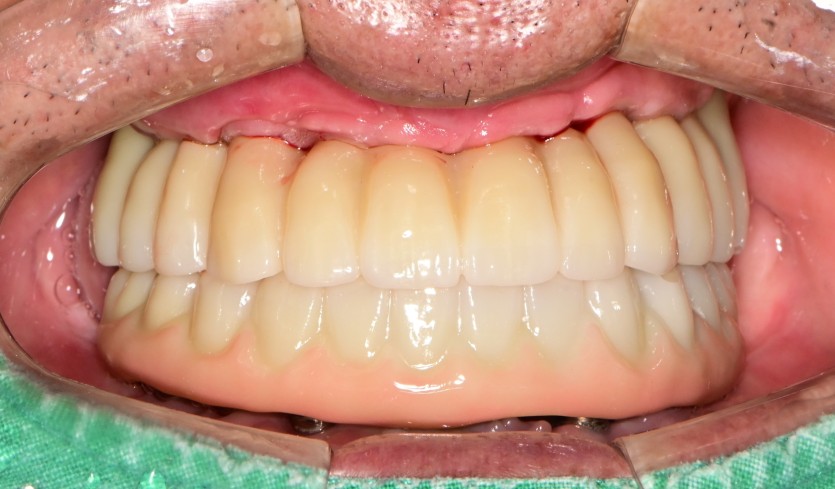

만 61세 전체 임플란트 증례

전체 임플란트 증례입니다.

(하악 풀아치-MUA 진행)

14개의 임플란트로 완성하였습니다.